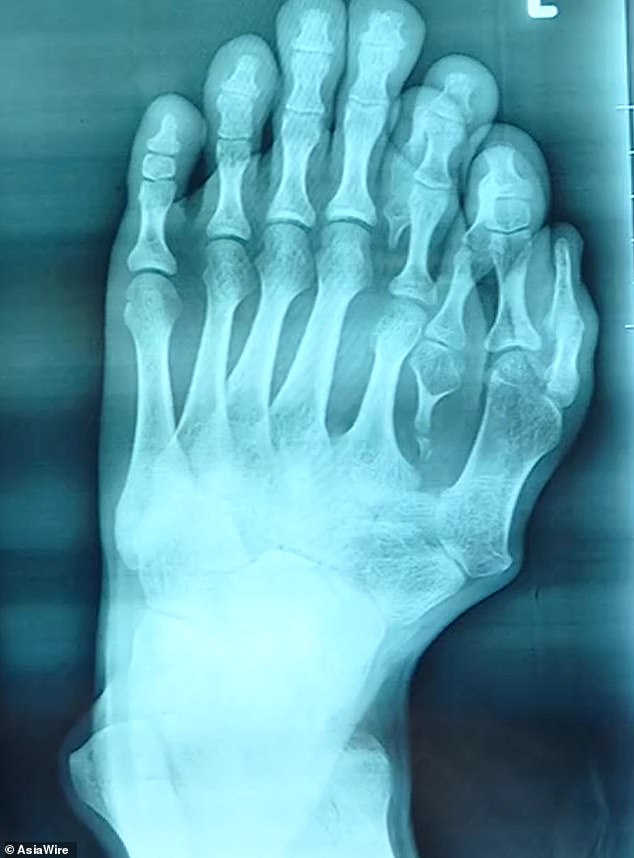

生まれつき左足の指が9本あった21歳の男性が正常な足にするための手術を受けた画像。

両親は「天からの贈り物」として対処しなかったため、男性は両親の反対を押し切って病院で手術を受けた。